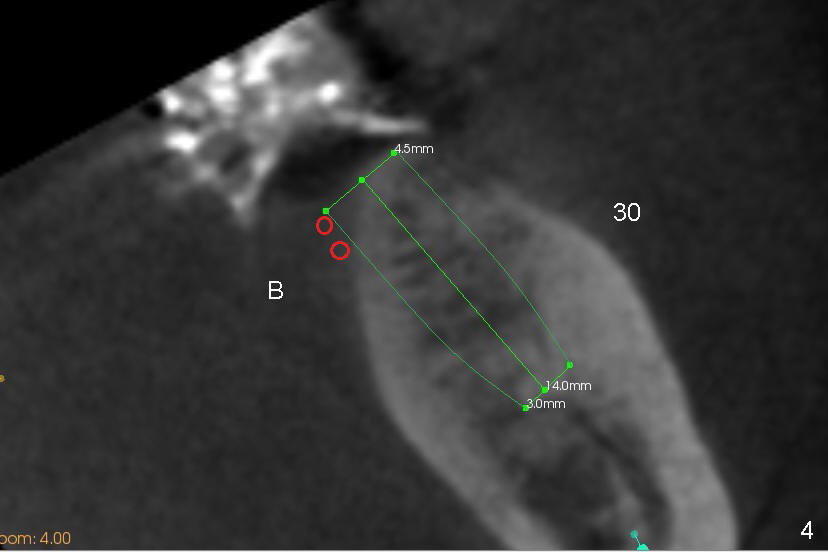

A 85-year-old man has poor dentition (Fig.9). Multiple implants are to be placed at one or two stages (#26-30). If primary stability is obtained for individual implants, they are splinted and immediate provisional is fabricated.

Fig.1-3 are CBCT sagittal sections of the lower right quadrant, whereas Fig.4-8 are coronal sections. The lower left quadrant has been restored.